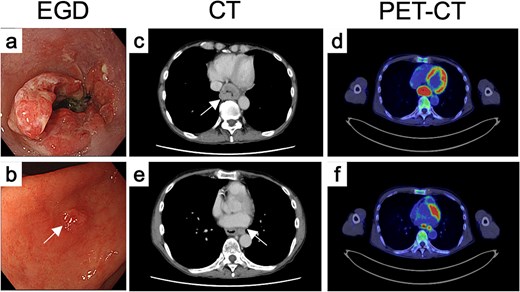

Endoscopy revealed a circumferential type 3 tumor with spontaneous bleeding, located 35–40 cm from the incisors (Fig. 1a). A slightly irregular elevated lesion ~1 cm in size was observed on the lesser curvature of the posterior gastric angle (Fig. 1b). Computed tomography (CT) demonstrated circumferential thickening of the lower esophagus with suspected extramural invasion (Fig. 1c) and enlarged regional lymph nodes near the aorta (Fig. 1e). Positron emission tomography (PET)-CT showed 18F-fluorodeoxyglucose (FDG) uptake corresponding to these lesions (Fig. 1d and f), but no abnormal uptake in the gastric wall.

Endoscopic, CT, and FDG-PET findings before treatment. Endoscopic findings of (a) the primary tumor and (b) the gastric IM before treatment. (c) CT and (d) FDG-PET findings of primary tumor before treatment. (e) CT and (f) FDG-PET findings of metastatic LN.